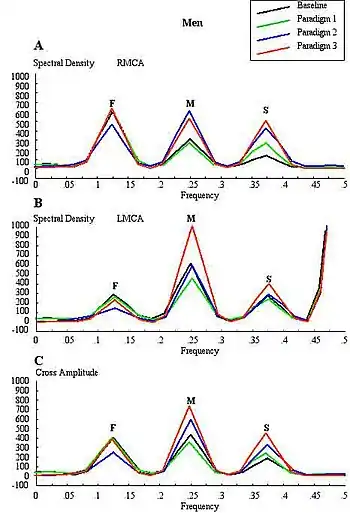

Conventional FTCD has limitations for the study of cerebral lateralization. For example, it may not differentiate the lateralising effects due to stimulus characteristics from those due to light responsiveness, and does not distinguish between flow signals emanating from cortical and subcortical branches of the cerebral arteries of the circle of Willis. Each basal cerebral artery of the circle of Willis gives origin to two different systems of secondary vessels. The shorter of these two is called the ganglionic system, and the vessels belonging to it supply the thalami and corpora striata; the longer is the cortical system, and its vessels ramify in the pia mater and supply the cortex and subjacent brain substance. Furthermore, the cortical branches are divisible into two classes: long and short. The long or medullary arteries pass through the grey substance and penetrate the subjacent white substance to the depth of 3–4 cm. The short vessels are confined to the cortex. Both cortical and ganglionic systems do not communicate at any point in their peripheral distribution, but are entirely independent of each other, having between the parts supplied by the two systems, a borderline of diminished nutritive activity.[18] While, the vessels of the ganglionic system are terminal vessels, the vessels of the cortical arterial system are not so strictly "terminal". Blood flow in these two systems in the middle cerebral artery (MCA) territory supplies 80% of both hemispheres,[19] including most neural substrates implicated in facial processing, language processing and intelligence processing at cortical and subcortical structures. The measurements of mean blood flow velocity (MFV) in the MCA main stem could potentially provide information about downstream changes at cortical and subcortical sites within the MCA territory. Each distal arm of the MCA vascular system could be separated into "near" and "far" distal reflection sites for the cortical and ganglionic (subcortical) systems, respectively. To accomplish this objective, one method is to apply Fourier analysis to the periodic time series of MFV acquired during cognitive stimulations. Fourier analysis would yield peaks representing pulsatile energy from reflection sites at various harmonics, which are multiples of the fundamental frequency.[20][21] McDonald in 1974 showed that the first five harmonics usually contain 90% of the entire pulsatile energy within the system of pressure/flow oscillations in the peripheral circulation. It could be presumed that each arm of the vascular system represents a single viscoelastic tube terminated by impedance, creating a single reflection site.[22] Psychophysiologic stimulation induced vasomotor activity at each terminal site sets up a standing sinusoidal wave oscillation, comprising a summation of waves due to effects of incident, reflected, and re-reflected waves from distal to proximal point of measurement. fTCDS studies are performed with the participant placed in a supine posture with their head up at about 30 degrees. The probe holder headgear (e.g. LAM-RAK, DWL, Sipplingen, Germany) are used with a base support on two earplugs and on the nasal ridge. Two 2-MHz probes are affixed in the probe holder and insonation performed to determine the optimal position for continuous monitoring of both MCA main stems at 50 mm depth from the surface of the probe. A serial recording of MFV for each stimulus is acquired and latter used for Fourier analysis. Fourier transform algorithm uses standard software (for example, Time series and forecasting module, STATISTICA, StatSoft, Inc.). The most efficient standard Fourier algorithm requires that the length of the input series is equal to a power of 2. If this is not the case, additional computations have to be performed. To derive the required time series, the data were averaged in 10-second segments for 1-minute duration or each stimulus, yielding 6 data points for each participant and a total of 48 data points for all eight men and women, respectively. Smoothing the periodogram values was accomplished using a weighted moving average transformation. Hamming window was applied as a smoother.[23][24] The spectral density estimates, derived from single series Fourier analysis, were plotted, and the frequency regions with the highest estimates were marked as peaks. The origins of the peaks are of interest in order to determine the reliability of the present technique. The fundamental (F), cortical (C) or memory (M), and subcortical (S) peaks occurred at regular frequency intervals of 0.125, 0.25, and 0.375, respectively. These frequencies could be converted to Hz, assuming that the fundamental frequency of cardiac oscillation was the mean heart rate. The fundamental frequency (F) of the first harmonic could be determined from the mean heart rate per second. For example, a heart rate of 74 bpm, suggests 74 cycles/60 or 1.23 Hz. In other words, the F-, C-, and S-peaks occurred at multiples of the first harmonic, at second and third harmonics, respectively. The distance of the reflection site for F-peak could be presumed to emanate from a site at D1 = wavelength/4 = cf/4 = 6.15 (m/s)/(4×1.23 Hz) = 125 cm, where c is the assumed wave propagation velocity of the peripheral arterial tree according to McDonald, 1974. Given the vascular tortuosity, the estimated distance approximates that from the measurement site in the MCA main stem, to an imaginary site of summed reflections from the upper extremities, close to the finger tips when stretched sideways.[25] The C-peak occurred at the second harmonic, such that the estimated arterial length (using common carotid c = 5.5 m/s)[26] was given by D2 = wavelength/8 = cf2/8 = 28 cm, and a frequency f of 2.46 Hz. The distance approximates the visible arterial length from the main stem of the MCA, through vascular tortuosity and around the cerebral convexity, to the end vessels at distal cortical sites such as the occipito-temporal junction on carotid angiograms of adults.[25] The S-peak occurred at the third harmonic, and may have arisen from an estimated site at D3= wavelength/16 = cf3/16 = 9.3 cm and a frequency f3 of 3.69 Hz. The latter approximates the visible arterial length of the lenticulostriate vessels from the main stem of the MCA on carotid angiograms.[27] Although not displayed, the fourth harmonic would be expected to arise from the MCA bifurcation in closest proximity to the measurement site in the main stem of the MCA. The pre-bifurcation length from the measurement point would be given by D4 = wavelength/32 = cf4/32 = 3.5 cm and a frequency f4 of 4.92 Hz. The calculated distance approximates that of the segment of MCA main stem just after the carotid bifurcation, where probably the ultrasound sample volume was placed, to the MCA bifurcation. Thus, these estimates approximate actual lengths. However, it has been suggested that the estimated distances may not correlate exactly with known morphometric dimensions of the arterial tree according to Campbell et al., 1989. The method was first described by Philip Njemanze in 2007, and was referred to as functional transcranial Doppler spectroscopy (fTCDS).[25] fTCDS examines spectral density estimates of periodic processes induced during mental tasks, and hence offers a much more comprehensive picture of changes related to effects of a given mental stimulus. The spectral density estimates would be least affected by artefacts that lack periodicity, and filtering would reduce the effect of noise.[28] The changes at the C-peak may show cortical long-term potential (CLTP) or cortical long-term depression (CLTD), which has been proposed to be suggest equivalents of cortical activity during learning[25] and cognitive processes. The flow velocity tracings are monitored during paradigm 1 comprising a checkerboard square as object perception are compared to whole face (paradigm 2) and facial element sorting task (paradigm 3). Fast Fourier transform calculations are used to obtain the spectral density and cross amplitude plots in the left and right middle cerebral arteries. The C-peak also called memory (M-peak) cortical peak could be seen arising during paradigm 3, a facial element sorting task requiring iterative memory recall as a subject constantly spatially fits the puzzle by matching each facial element in paradigm 3 to that stored in memory (Paradigm 2) before proceeding to form the picture of the whole face.